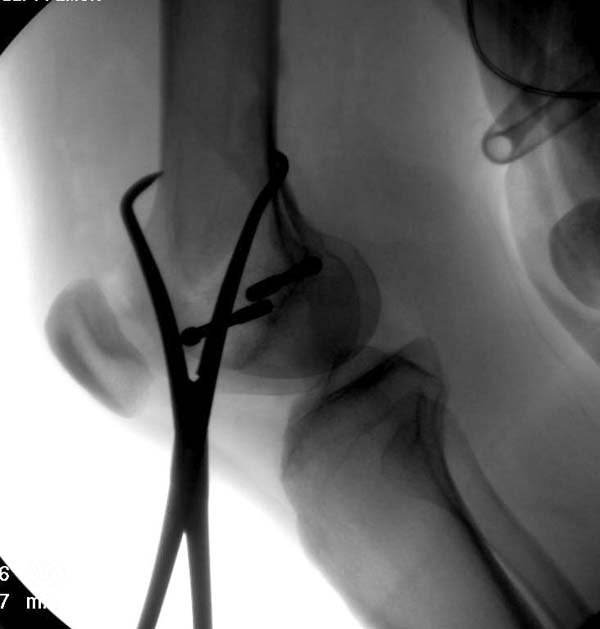

[Ortho] Нелеченный перелом Hoffa

Здесь представлены различные варианты фиксации перелома, а также снимки

комбинации перелома с повреждением хряща (12-19). Пластика хряща

OsseoFit и установка custom made plate.